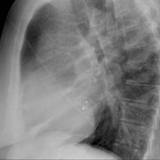

ASD 3 Lat